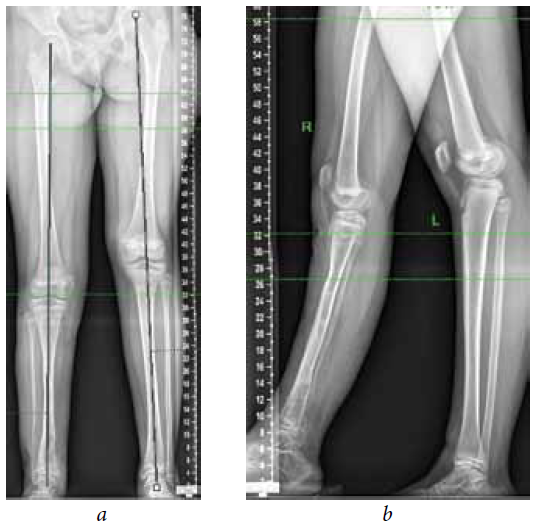

The second stage of treatment was the recommended correction of the resulting multiplane deformities of the affected lower extremity (mMPTA was 94°, mLDTA was 71°, aPPTA was 90°, and aADTA was 59°, shortening the affected lower limb by 8.0 cm). For lengthening and deformity correction of the right lower limb, the patient underwent preoperative planning for deformity correction with the exception of osteotomies in the area of consolidated pseudoarthrosis at the age of 9 years. According to the plan, a two-level osteotomy of the shin bones was performed, as along with lengthening by 5 cm by the Ilizarov method. The deformity was corrected using a repositional unit with Ortho-SUV computer navigation properties. The period of deformity correction was 58 days, and the external fixation period was 247 days. At the end of the fixation period, a recurrence of deformities of the tibial bones was detected with the formation of a deformity apex at the level of the proximal and distal tibial growth zones (mMPTA was 94°, mLDTA was 82°, aPPTA was 86°, and aADTA was 80°) (Fig. 1–4). We applied hemiepiphysiodesis to correct the recurrence of valgus deformity of the tibia. The period of deformity correction was 269 days. The reference angles values of the tibia were within the accepted ranges.

Fig. 3. Preoperative planning for deformity correction in a patient with cCPASB using specialized software: а — anterior-posterior view; b — lateral view

Fig. 4. Roentgenograms of the patient with cCPASB following deformity correction of the bones of the right tibia: а — anterior-posterior view; b — lateral view